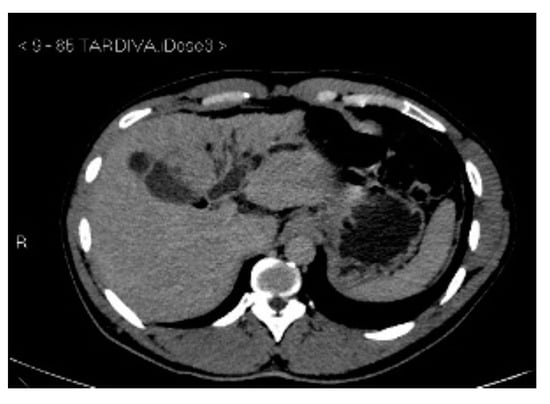

Subsequently, an upper-abdomen Computed Tomography (CT) scan and liver Magnetic Resonance Imaging (MRI) were performed (Figure 1, Figure 2, Figure 3, Figure 4, Figure 5, Figure 6 and Figure 7).

Figure 3.

CT delayed phase.

A mass of 1.8 cm was detected within the biliary branch for the third hepatic segment, characterized by nodular impregnation in the arterial phase and irregular and partial washout in the portal venous phase. These findings were compatible with a heterologous lesion, although it was not possible to perform a diagnosis among HCC, intrahepatic CCA or other pathological lesions.

HCC typically has an increased arterial blood supply, so it usually shows hyperattenuation in the arterial phase and hypoattenuation in the portal venous phase, compared to the hepatic parenchyma.

Most HBDTTs should show the same enhancement pattern. However, some HCCs can show iso- or hypoattenuation in the arterial phase, with the enhancement in the arterial phase inversely correlated with the degree of blood clots and necrosis. So, hypoattenuation in the portal venous phase seems to be the most important imaging feature to distinguish HCC with BDTT from perihilar CCA [17].

In conclusion, the diagnosis of HCC with BDTT can be reasonably considered in the presence of lesions of both hepatic parenchyma and bile ducts with a cirrhotic underlined liver disease, especially if they show typical washout in the portal venous phase.